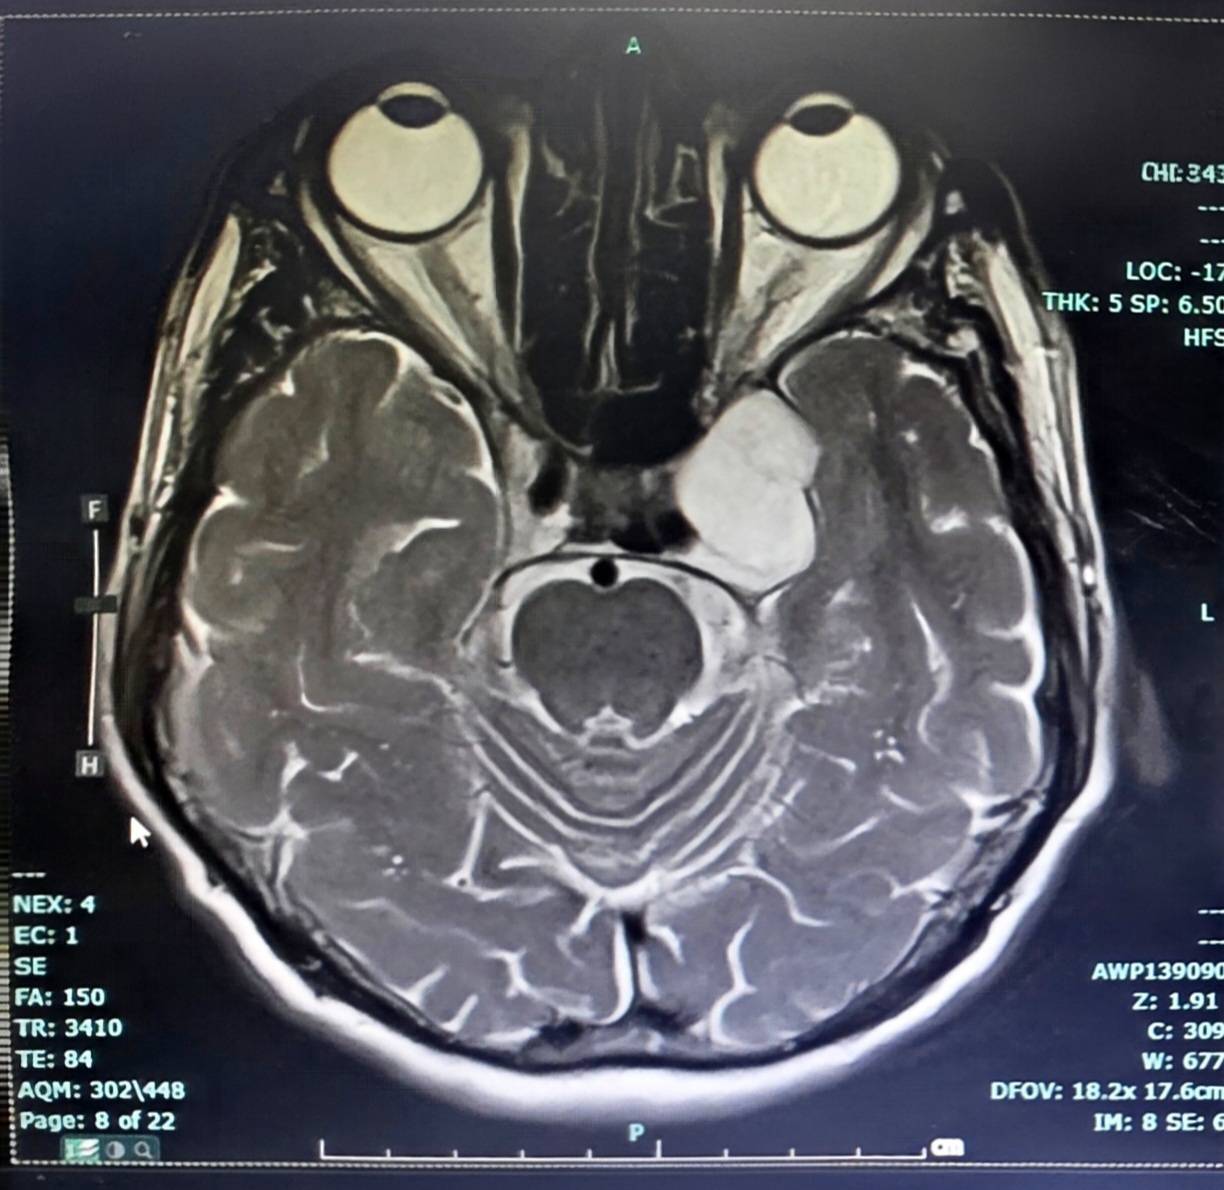

27 มีนาคม 2569 เมื่อวันที่ 26 มี.ค.2569 เพจ โรงพยาบาลลำปาง โพสต์ข้อความระบุถึงความสำเร็จในการรักษาผู้ป่วย รายละเอียดระบุว่า ในวันที่ 24 มีนาคม 2569 โรงพยาบาลลำปางประสบความสำเร็จในการผ่าตัดเนื้องอกฐานสมอง (Skull Base Surgery) บริเวณโพรงไซนัสคาเวอร์นัส (Cavernous Sinus Tumor) ด้วยเทคนิค Endoscopic Transorbital Approach (ETOA) ซึ่งเป็นการผ่าตัดผ่านกล้องส่องทางเบ้าตา ซึ่งจัดเป็นการผ่าตัดแผลเล็ก (Minimal Invasive Surgery) เป็นเทคโนโลยีศัลยกรรมขั้นสูงที่ช่วยลดการบาดเจ็บต่อสมองและโครงสร้างสำคัญ เมื่อเทียบกับการผ่าตัดแบบเปิดกะโหลกขนาดใหญ่ และนับได้ว่าเป็นการผ่าตัด ETOA เพื่อผ่าตัดเนื้องอกสมอง สำเร็จเป็นเคสแรกของเขตสุขภาพที่ 1 กระทรวงสาธารณสุข

การผ่าตัดดำเนินการโดย นพ.เอื้ออังกูรยิ์ สิทธิมงคล ศัลยแพทย์ระบบประสาท โรงพยาบาลลำปาง การผ่าตัดเป็นไปอย่างราบรื่น สามารถนำก้อนเนื้องอกออกได้สำเร็จ หลังผ่าตัดผู้ป่วยฟื้นตัวดี และสามารถกลับมาใช้ชีวิตประจำวันได้ตามปกติ